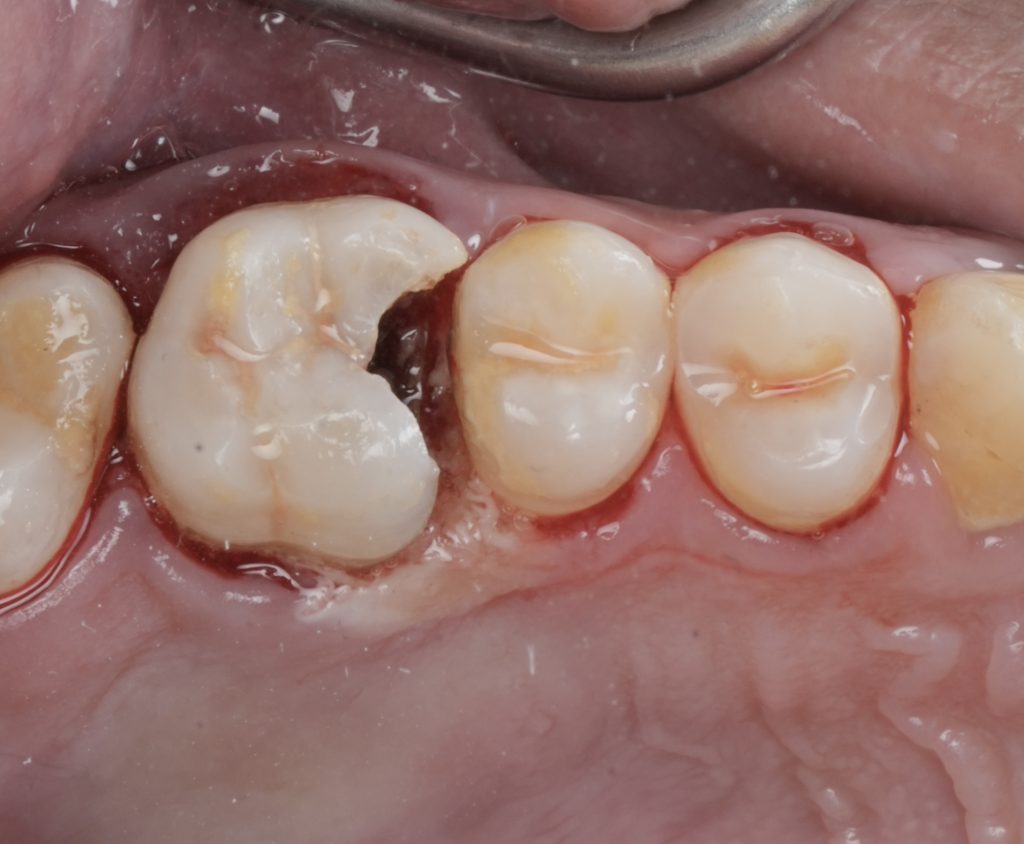

Core Build-Up

A bonded core build-up was performed under rubber dam isolation to reinforce remaining tooth structure. The build-up aimed to:

- Seal the endodontic access

- Distribute occlusal stresses

- Create a stable foundation for cuspal coverage

Cuspal Coverage Restoration

Given the extent of structural loss and endodontic access, cuspal coverage was indicated to prevent fracture. Occlusal anatomy was rebuilt using a biomimetic approach, restoring:

- Functional cusp anatomy

- Proper occlusal contacts

- Axial load distribution

The restoration was finished and polished to achieve smooth margins and harmonious occlusion.